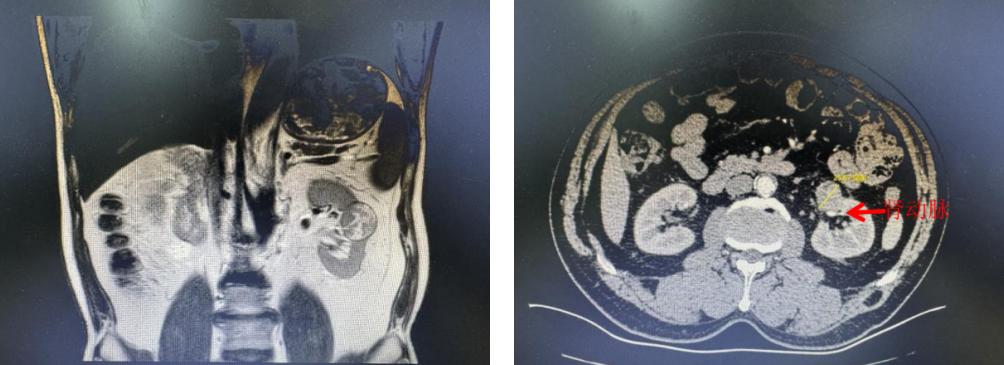

精准取舍 巨大肿瘤的“肾功保全术”

另一例病例中,患者肾脏肿瘤体积巨大,需实施解剖性半肾切除术,既要完整切除肿瘤组织,又要最大限度保留健康肾单位,对手术精准度和时间控制提出严苛要求。

术中,团队凭借对肾脏内部解剖结构的准确掌握,结合机器人器械的稳定操控,精准阻断目标段动脉,避免健康肾组织缺血损伤;精准楔形切除肿瘤,确保无肿瘤残留;精细缝合重建集合系统,避免肾盂肾盏损伤。整个手术热缺血时间严格控制在20分钟以内,最大限度地保护术后残留肾功能的恢复潜力。

肾肿瘤影像